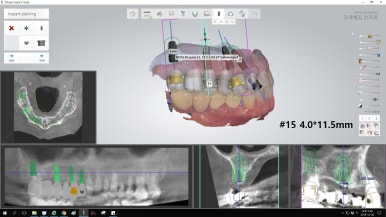

어금니 타치과에서 실패한 인플란트(찢어져 있어서 임플란트 머리를 올리지 못한 상태)는 제거하고

어금니 빈 곳에 임플란트를 3개 심고 머리는 4개 만들어 어금니 4개 완성

및 앞니부위에는 기존 흔들리고 덜렁거리는 앞니 브릿지 제거하고

썩은 뿌리로 인한 염증치아의 썩은 뿌리만 남은 것 발치 후

앞니용 얇은 임플란트를 식립하였습니다.

네비게이션 임플란트를 사용하여 적절한 간격과 각도를 유지하였고

특히 앞니의 경우 뼈가 매우 얇았으나 내비게이션을 사용하여

뼈가 얇아도 뼈를 뚫고 나갈 위험이 없이 적절한 뼈 위치에 임플란트를 식립하였습니다.